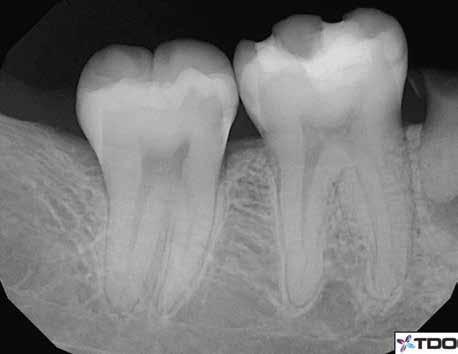

1. a–g. ábrák: A direkt pulpasapkázás lépései. Kiindulási bitewing-felvétel: A meglévő restaurátum közel helyezkedett el a pulpakamrához (a). Kiindulási periapicalis felvétel: Nincs periapicalis elváltozás fennállására utaló jel (b). A pulpaexpozíció (c). A vérzéscsillapítás céljából 20 másodpercen keresztül steril vattagombóccal történő kompressziót követően látható pulpaseb (d). A pulpasapkázás céljából behelyezett anyag, a széli részek tisztázása előtt készült felvétel (e). A röntgenárnyékot nem adó ideiglenes tömés behelyezése után készült felvétel (f). Az első ülés végén a röntgenárnyékot nem adó ideiglenes töméssel ellátott fogról készített röntgenfelvétel (g).

2. ábra: A hat hónapos kontroll alkalmával készített röntgenfelvételen vastag dentinhíd látható a pulpasapkázó anyag alatt.

3. ábra: A hároméves kontroll alkalmával készített röntgenfelvételen megfigyelhető a restaurátum pontos illeszkedése.

A kezelést követően a beteg tünetmentes volt. A kérdéses fog a kontrollvizsgálatok során végzett szenzibilitástesztekre fiziológiás reakciókat adott. A hat hónapos kontroll alkalmával készített röntgenfelvételen a sérülésnek megfelelően széles dentinhidat észleltünk (2. ábra). A restaurátum a hároméves kontroll során is megfelelőnek bizonyult (3. ábra)